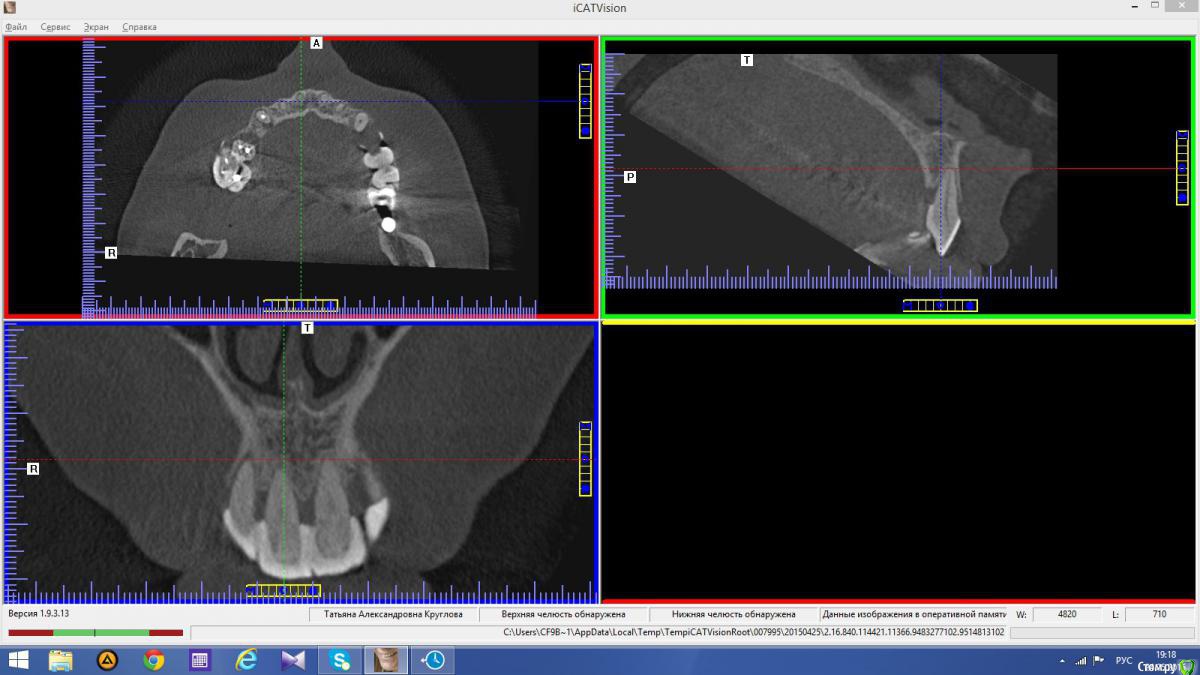

Популярный пост Abuk Опубликовано 24 ноября, 2015 Популярный пост Поделиться Опубликовано 24 ноября, 2015 Планировали 8 имплантатов.Буду рад конструктивной критике.Фото с мокап.Через 6 днейДалее хотели поставить 6 ки, она отказалась (не хотели синусы)и решили все по-другому .Через 2мес пришла с отколотыми консолями )Прошу прощения ,что ортопедию выложил не в том разделе), не хотел делить. 26 1 Ссылка на комментарий

Abuk Опубликовано 24 ноября, 2015 Автор Поделиться Опубликовано 24 ноября, 2015 Снимки не могли бы показать? .все что есть готовое. Ссылка на комментарий

Abuk Опубликовано 24 ноября, 2015 Автор Поделиться Опубликовано 24 ноября, 2015 (изменено) Радикально Вы. Что оставили ей после имплантации-это инд аббатменты? На них мокап одели и нагрузили сразу? У всех был торк хороший? Или это временные абб? Что за систему использовали? В планах консоль назад, правильно я понимаю?Спасибо.увидев такую работу,сам так же подумал бы). Но там подвижность 2-3 ст. ближе к 3. Мосты болтались ,2 ки в хлам. 1 ки только стабильны. Снимал мосты,проводил кюретаж. Решил дернуть.Абатманы временные, тех. сделал на них коронки. Система анкилоз. Работа,на посл. фото, постоянная . Имплы в области 4 и по одному моляру ,консоли. Мок ап был до имплантации . По нему шаблон. Стабильность 15 -20 на 23 , остальное больше 30. Изменено 24 ноября, 2015 пользователем Abuk 1 Ссылка на комментарий